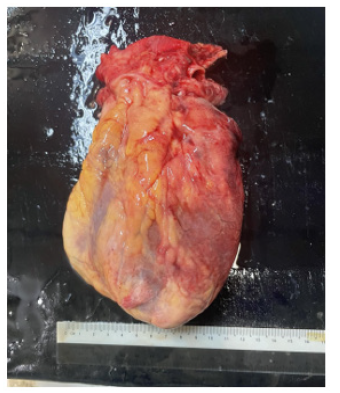

Figures 6-7 are post-mortem examination of anterior and lateral surface heart. They revealed hyperemia of whole surface of left ventricle indicating very extensive myocardial infarction.

Figure 6: Post-mortem examination of anterior surface heart showing hyperemia over surface of left ventricle.

Figure 7: Post-mortem examination of lateral view heart showing hyperemia over surface of left ventricle.